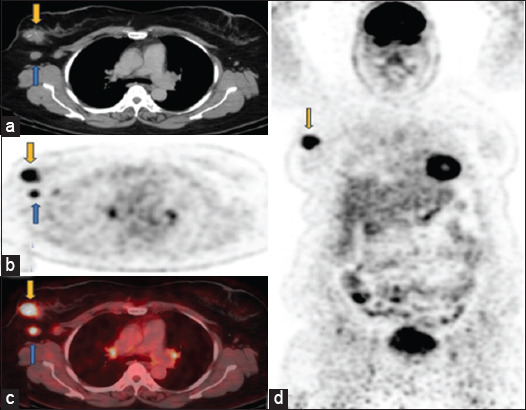

Case description: Here, we describe a patient who was diagnosed with axillary diffuse large B cell lymphoma (DLBCL) in a cancer hospital during a staging work-up for suspected breast cancer. Breast cancer was staged as Stage IIA and DLBCL as Stage IE. She was given three cycles of rituximab, cyclophosphamide, vincristine, doxorubicin, and prednisolone (R-CHOP) protocol. Interim positron emission tomography scan showed a complete metabolic response (Deauville score 2). She was given one more cycle of R-CHOP. Then, she had right breast-conserving surgery with axillary lymph node dissection in August 2023. Histopathology report showed residual disease with ductal carcinoma in situ. She was recommended weekly paclitaxel for 12 cycles and trastuzumab and pertuzumab for 1 year. She is currently having her adjuvant systemic therapy, after which she will be planned for local radiation. Endocrine treatment will be started once chemotherapy is completed.